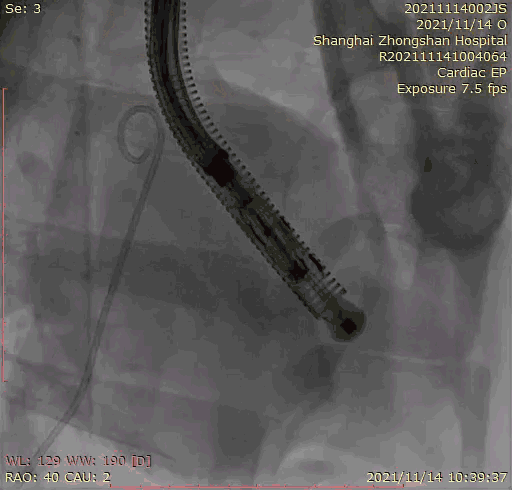

本次臨床前研究經(jīng)右側頸靜脈置入LuX-Valve Plus輸送系統(tǒng)可調彎鞘管,在DSA及超聲引導下將人工三尖瓣瓣膜植入到原有三尖瓣位置,利用獨特的錨定技術將人工瓣膜支架可靠固定在預定的位置。

上海中山醫(yī)院葛均波院士、錢菊英院長、周達新教授、潘文志教授、潘翠珍教授、李偉教授共同完成此次臨床前研究。術后葛均波院士對Lux-Valve Plus的器械操作性能給予了高度評價,DSA和超聲影像也顯示出在本次研究中Lux-Valve Plus的安全性和有效性俱佳。